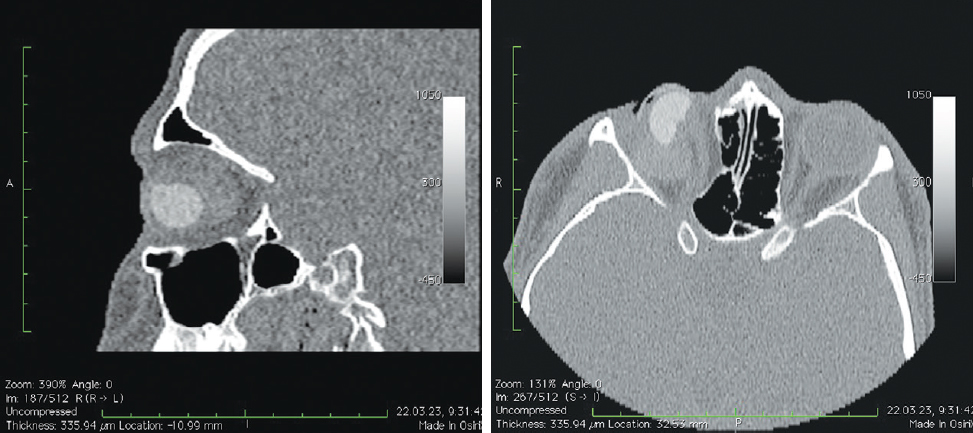

Рис. 9. Пациент, 57 лет. 3 года после операции с имплантацией эндопротеза с изменённой геометрией, дефект передней поверхности культи, обнажение края имплантата. МСКТ-исследование

Fig. 9. Patient, 57 y. o. 3 years after surgery with implantation of an endoprosthesis with modified geometry. Defect of the anterior surface of the stump, exposure of the orbital implant

При анализе рентгенологических изображений после выполнения МСКТ-диагностики у всех обследованных пациентов по описанному ранее алгоритму [16] нами было выявлено изменение размеров и геометрии орбитальных сфер в виде «срезанной» части (рис. 8). Параметры изменённой части, как и размеры самих имплантатов, были различны (табл. 1–3). Исходные параметры (диаметры) орбитальных сфер — 18, 19 и 20 мм. При компьютерно-томографическом исследовании на полученных изображениях мы анализировали размеры имплантированных материалов, определяя объём вкладышей через радиус и высоту срезанной части по формуле: V = 1/3πh2(3r – h), где π — константа, равная 3,14; r — радиус шара; h — высота шарового сегмента имплантата.

Анализируя полученные данные, мы установили, что размеры изменённой геометрии имплантированных орбитальных вкладышей отличались, потери объёма при исходном диаметре 20 мм составили в среднем 0,4038 см3, при диаметре 19 мм — 0,340 см3, при диаметре 18 мм — 0,298 см3 (рис. 7–11).

В мягких тканях вокруг изменённых имплантированных сфер нами выявлены уплотнения, без признаков кальцинации и деструкции стенок орбиты (рис. 7, 8). Кроме того, у одной пациентки было отмечено не только изменение геометрии сферы в виде срезанной части (рис. 10, а), но и наличие множества фрагментов полимерного материала идентичной рентгенологической плотности. Эти фрагменты имплантата находились за задним полюсом полимерного вкладыша в мягких тканях до вершины орбиты (рис. 10, b).